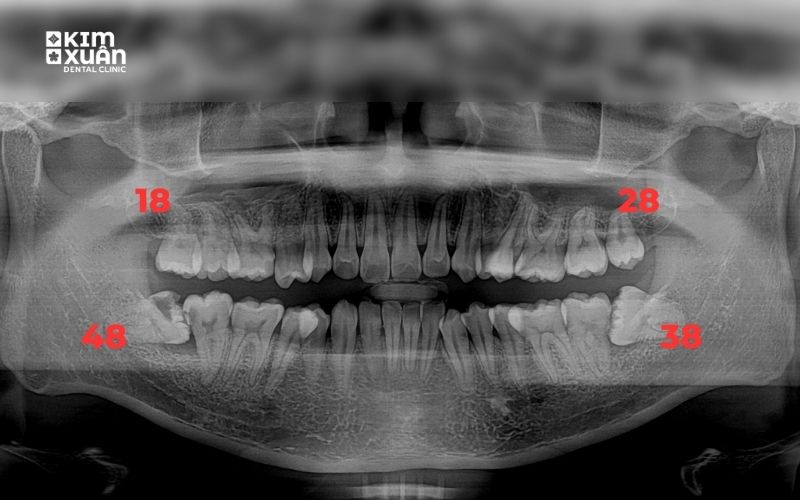

Răng khôn (răng số 8) là chiếc răng mọc cuối cùng trên cung hàm, thường xuất hiện trong độ tuổi từ 17 - 25. Thời điểm này, xương hàm đã phát triển hoàn chỉnh, không còn nhiều khoảng trống, khiến răng khôn rất dễ mọc lệch, mọc ngầm hoặc kẹt trong xương hàm thay vì mọc thẳng như các răng khác.

4.1. Vị trí và góc mọc của răng khôn

Răng khôn mọc thẳng thường dễ nhổ, ít xâm lấn nên chi phí thấp. Ngược lại, răng khôn mọc lệch, mọc ngang (45 - 90 độ) hoặc mọc ngầm trong xương hàm sẽ khó can thiệp hơn, cần bóc tách mô và chia thân răng, do đó chi phí nhổ răng khôn cao hơn.

Với răng khôn mọc ngầm hoặc mọc khó, bác sĩ thường chỉ định tiểu phẫu để đảm bảo an toàn, tránh ảnh hưởng đến dây thần kinh hàm dưới và hạn chế biến chứng sau nhổ.

Thăm khám tổng quát và chụp phim X-quang trước khi nhổ

Bác sĩ trực tiếp đánh giá vị trí răng, mức độ khó và nguy cơ liên quan